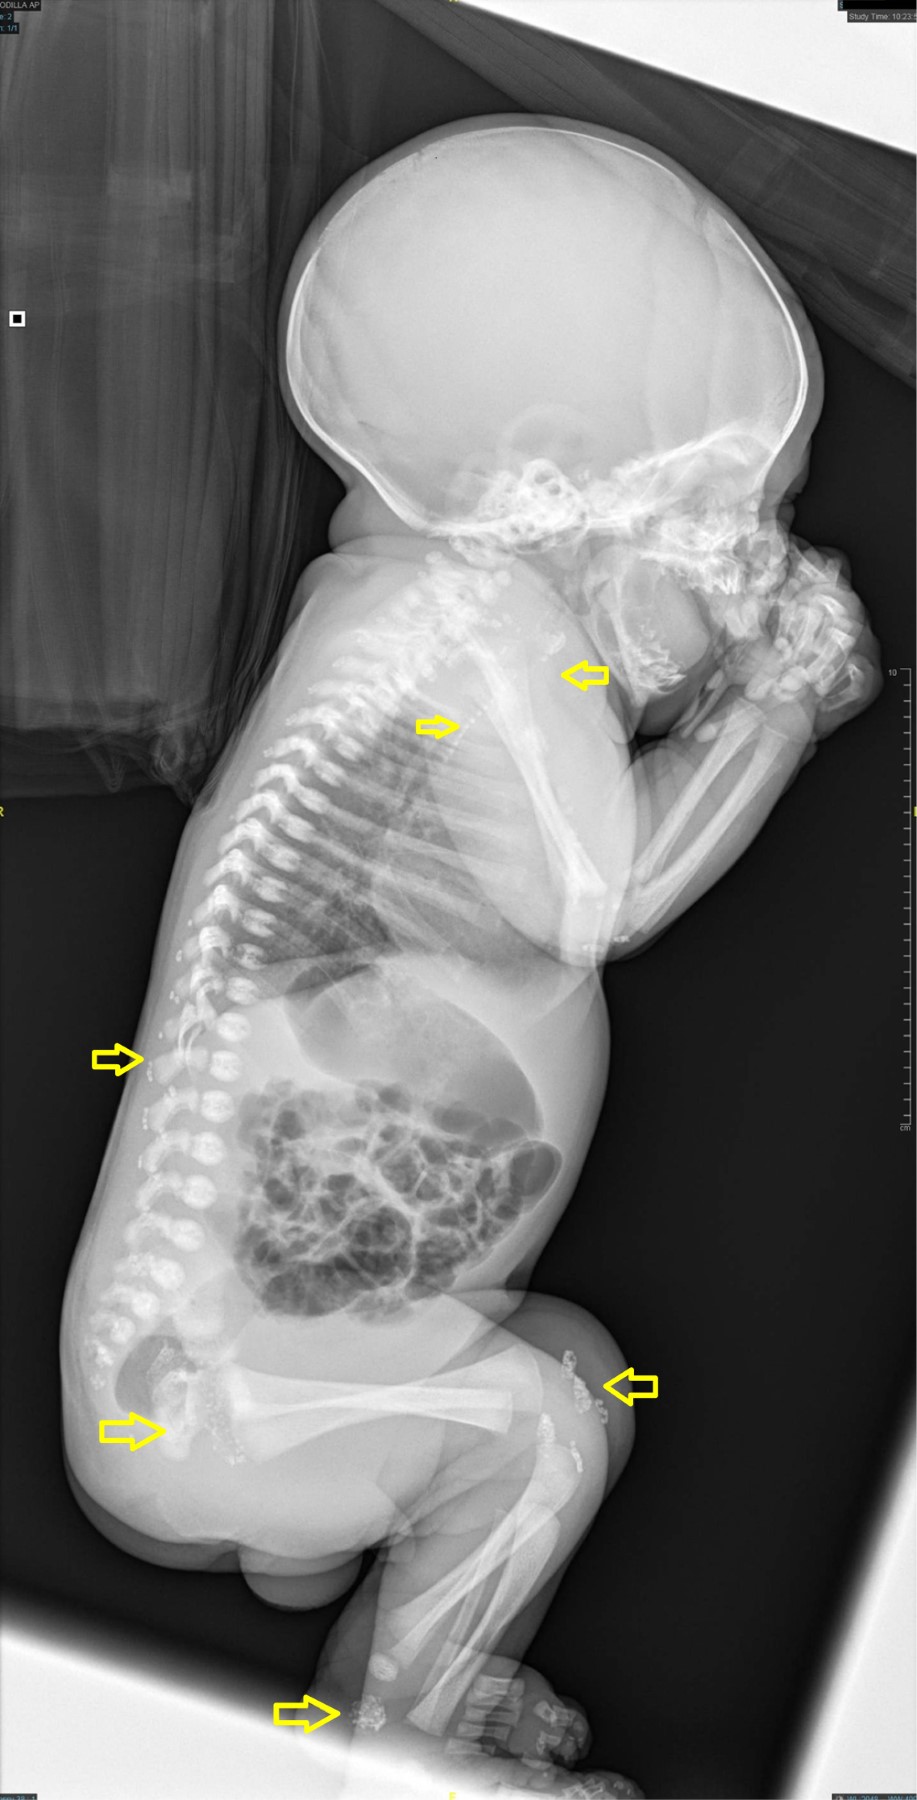

Chondrodysplasia punctata in neonate

We present the radiographic images of a newborn in whom a diagnosis of chondrodysplasia punctata was reached. Patients with this disorder have pinpoint calcifications in multiple joints.

Figure 1